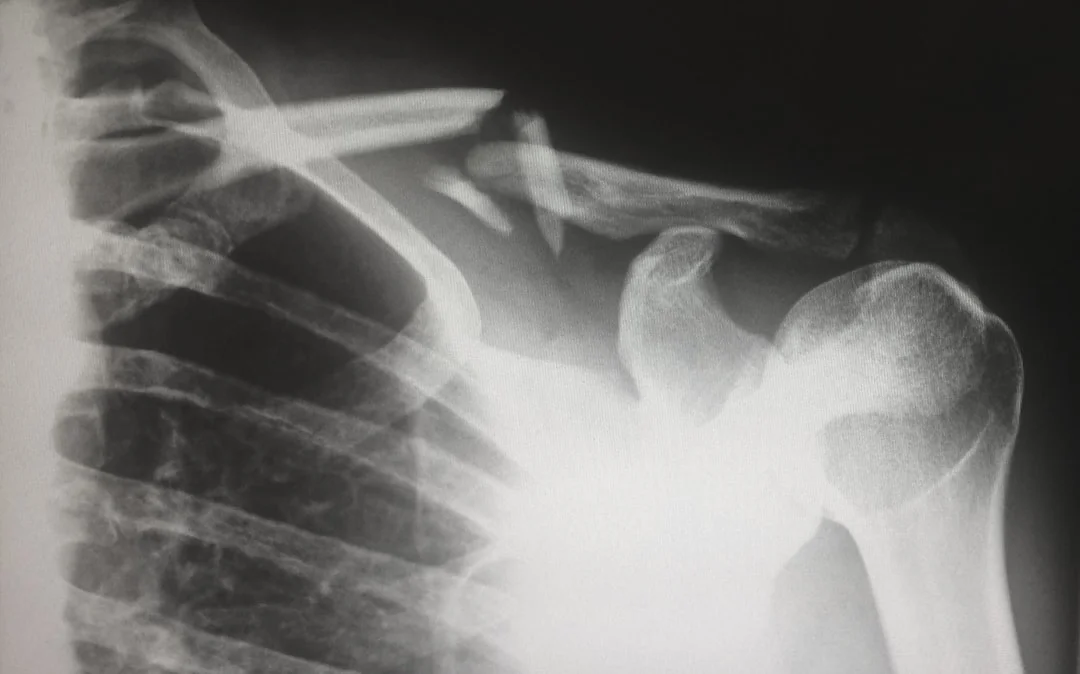

Serviciile de ortopedie de la Centrul Medical Rimmed oferă diagnostic și tratament specializat pentru afecțiunile aparatului locomotor - oase, articulații, mușchi și tendoane.

• Fracturi simple și complexe

• Radiografii simple